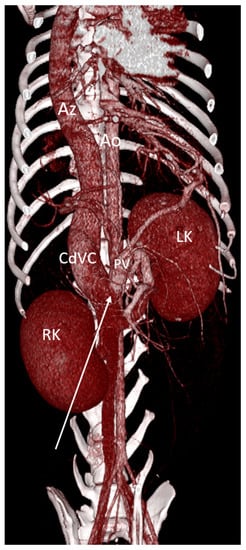

Congenital Absence of the Portal Vein (Aplasia and Atresia)